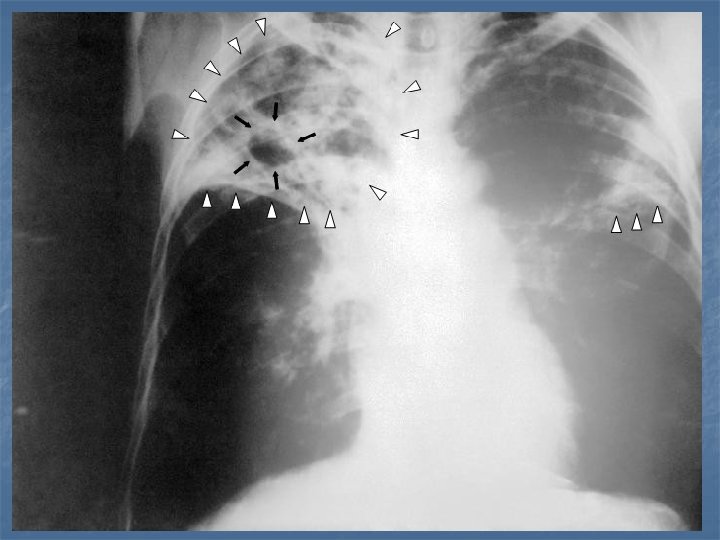

LOCALIZARILE TBC: - pulmonara - SNC - renala - osoasa - cardiaca

GENUL MYCOBACTERIUM TBC PULMONARA